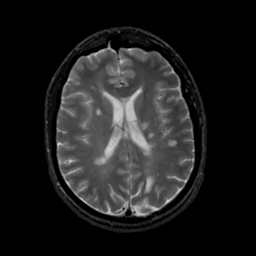

MR Study #18, July 21, 1991 -- Slice #30